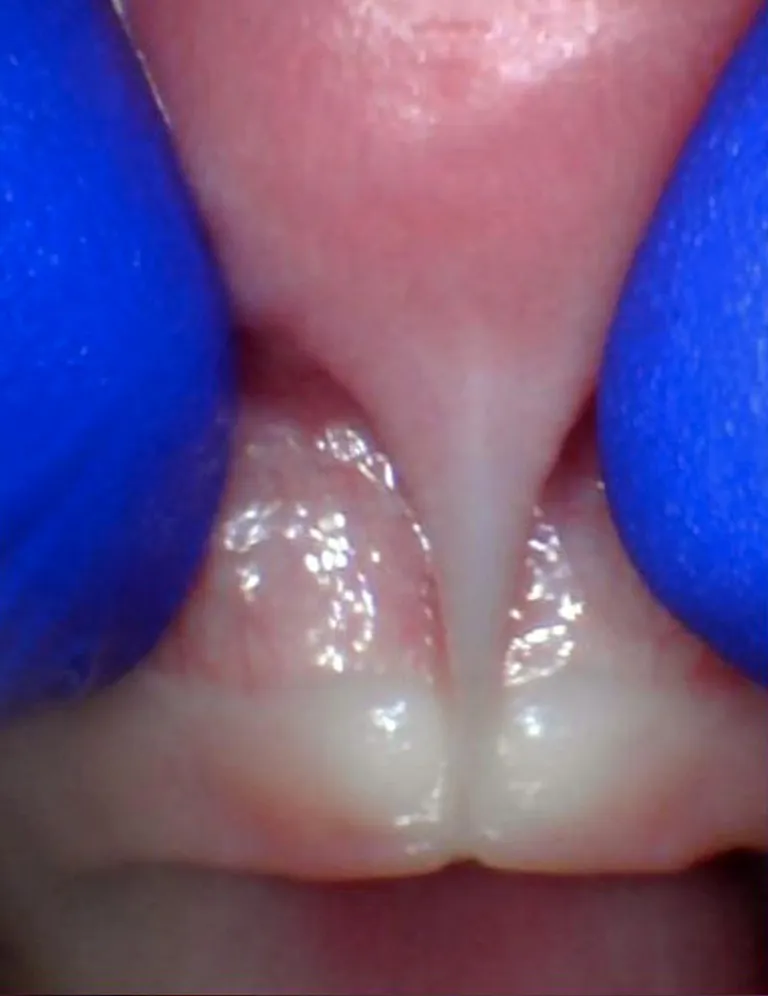

Le frein labial restrictif correspond à une anomalie où la lèvre supérieure est restreinte et ne peut pas bouger normalement. Il peut rendre difficile l'allaitement, l’alimentation, la parole et le brossage des incisives supérieures ; il peut également entraîner un diastème important (espace entre les dents) lorsqu’il est plus large que 2mm.

Il existe des spectres de restriction (site Tongue-Tie Alabama du Dr R. Baxter, Spectrum of lip/tongue restriction in infant/children), il n'existe pas une seule apparence. Il est donc important de comprendre la notion de symptomatique versus asymptomatique : un frein qui semble court ne sera opéré que s'il impacte la bonne fonction linguale, labiale ou jugale.

Photos ci-dessous issues du site Tongue-Tie Alabama avec l'accord de R. Baxter.

Enfant - Spectre de restrictions d'un FR labial